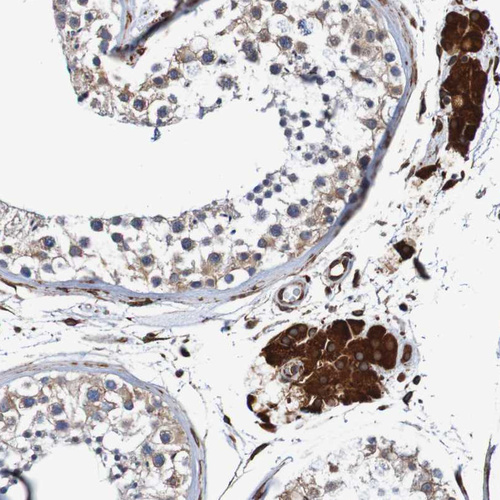

Immunohistochemical staining of human tonsil shows strong cytoplasmic positivity in non-germinal center cells.